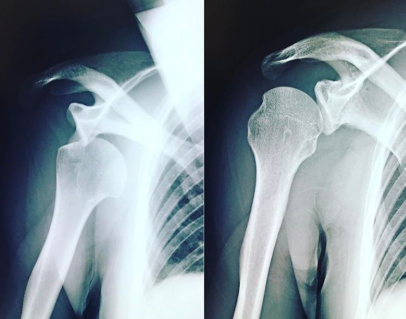

👇左が脱臼してる状態

肩甲上腕関節(=肩関節)でいえば、

上腕骨頭が

関節窩の中央付近にあって

動作の中で多少ズレても

すぐに中央へ戻れること

逆に、これが外れたまま

戻ってこられなくなったのが

〝脱臼〟です